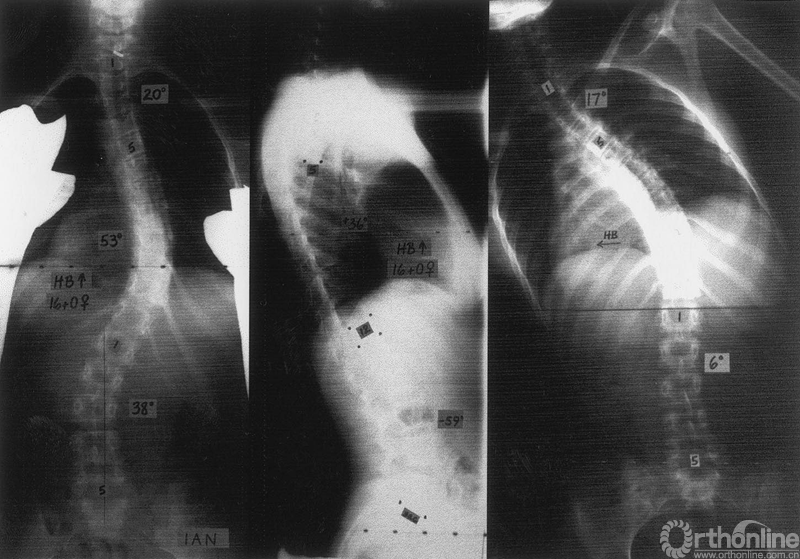

MT为弯(53°),PT区域在上,TL/L区域在下,矢状面为非结构性(分别为17°和6°)